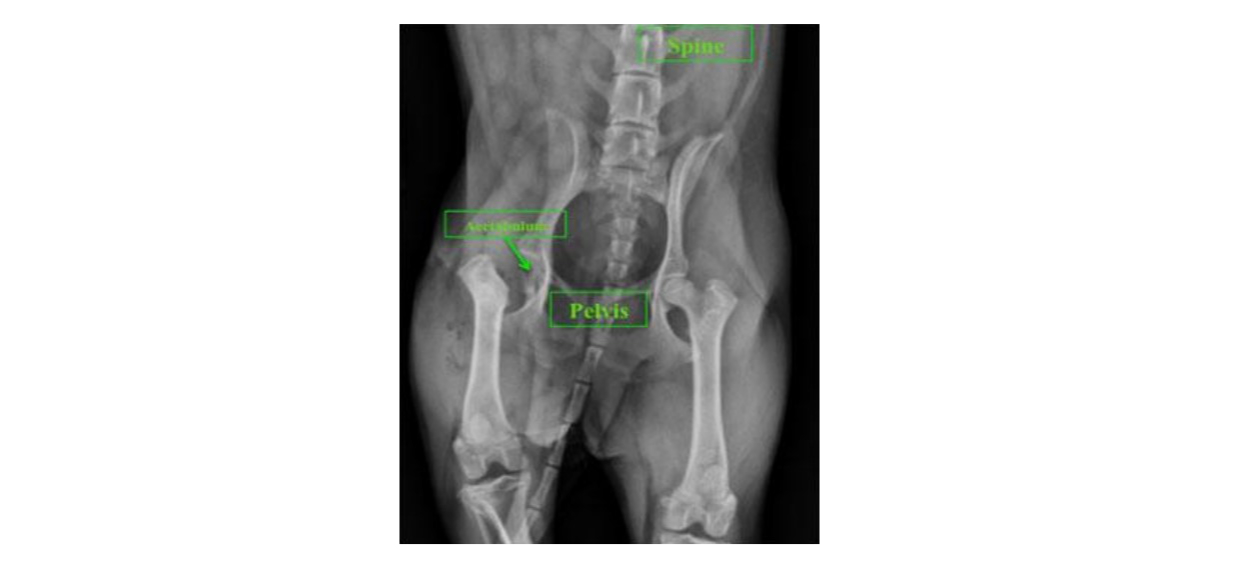

Diagnostic imaging such as radiography (X-rays) or CT may be used to determine the underlying cause of hip pain/lameness and potentially plan for surgical procedures that preserve the hip joint. The choice to perform an FHO is determined by the patient’s condition and discussion between the owner and veterinarian. Below is a radiograph of a patient suspected to have aseptic necrosis of the femoral head. Notice the difference in density and appearance between the left and right femoral head. An FHO was chosen for this patient.

After excision, the joint capsule and musculature are closed over the acetabulum and the incision is closed with suture material. Postoperative radiographs are taken to confirm proper excision.